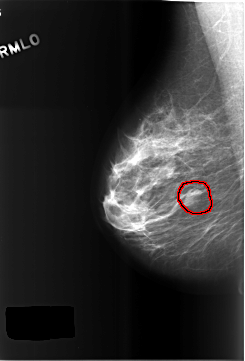

C_0510_1.RIGHT_MLO

RIGHT_MLO LINES 5768 PIXELS_PER_LINE 3912 BITS_PER_PIXEL 12 RESOLUTION 50 OVERLAY

FILE: C_0510_1.RIGHT_MLO.OVERLAY

TOTAL_ABNORMALITIES 1

ABNORMALITY 1

LESION_TYPE MASS SHAPE OVAL MARGINS CIRCUMSCRIBED

ASSESSMENT 3

SUBTLETY 4

PATHOLOGY BENIGN

TOTAL_OUTLINES 1